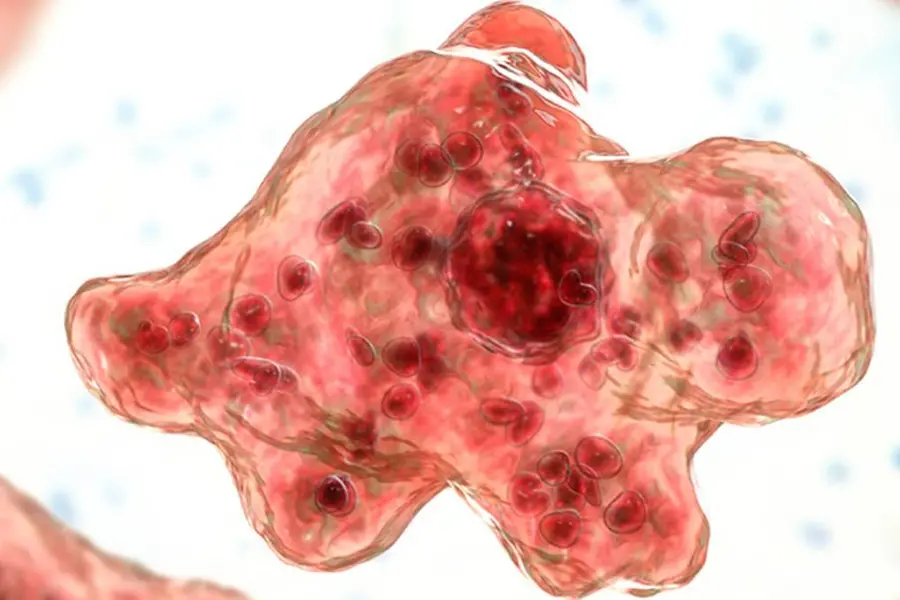

Amoebic meningoencephalitis, a lethal infection of the central nervous system caused by free-living amoebae, typically originates from freshwater bodies such as lakes, rivers, and streams.